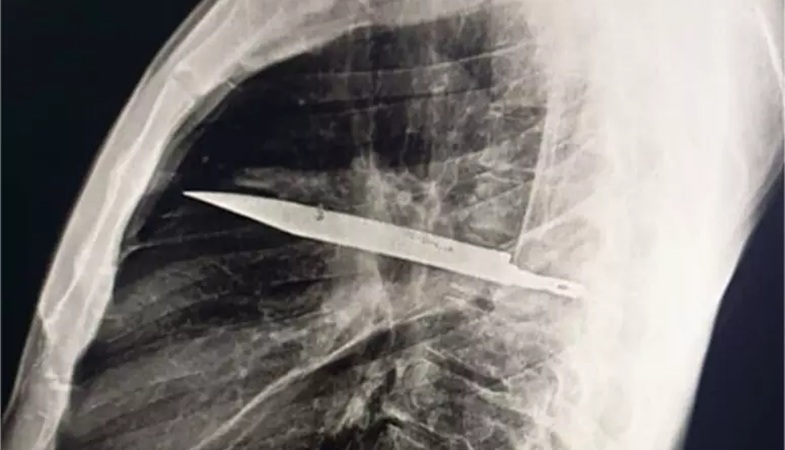

Homem se queixa de secreção no peito e descobre faca alojada há oito anos | Foto: Reprodução

Um homem de 44 anos descobriu, de forma surpreendente, que carregava uma faca alojada no peito havia oito anos. O caso, registrado na Tanzânia e publicado na Biblioteca Nacional de Medicina dos Estados Unidos, deixou médicos perplexos: o paciente não apresentava dor, febre, dificuldade para respirar, tosse ou qualquer alteração nos sinais vitais. Foi uma secreção abaixo do mamilo que motivou a investigação.

Durante todos esses anos, o homem não apresentou sintomas. Somente quando a secreção surgiu é que procurou atendimento e os médicos decidiram realizar exames de imagem -- e a radiografia revelou a lâmina atravessada no peito, sem atingir órgãos vitais.